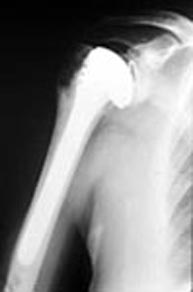

A los pacientes que no responden al tratamiento conservador y no aceptan las limitaciones funcionales que les provoca la enfermedad articular se les aconseja efectuar una intervención quirúrgica para colocar una prótesis o artroplastia de hombro. Existen diversos modelos y posibilidades que el cirujano ortopeda especialista en hombro deberá adaptar a cada paciente en particular.

Los resultados de las prótesis de hombro actualmente son muy satisfactorios permitiendo eliminar el dolor así como mejorar de forma importante la movilidad y la función de la articulación. Pueden haber complicaciones como por ejemplo una infección, que deberán prevenirse utilizando una técnica quirúrgica rigurosa y extremando todas las medidas de seguridad.